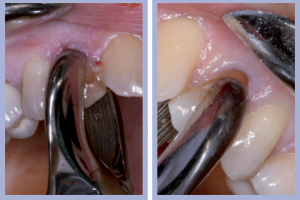

- Fig. 3 – Ortopantomografia iniziale

L’esame clinico iniziale (Figg. 1, 2) metteva in evidenza una buona situazione dento-parodontale generale; l’igiene orale e la collaborazione da parte della paziente, fortemente motivata alla soluzione del problema, erano ottime. L’esame radiologico ortopanoramico iniziale (Fig. 3) mostrava una buona quantità di osso apicalmente alle radici degli elementi decidui che apparivano sottili e parzialmente riassorbite. Il progetto terapeutico prevedeva un posizionamento implantare post-estrattivo immediato associato a carico immediato non funzionale tramite l’utilizzo di monconi temporanei e corone in resina precedentemente allestite, da ribasare in bocca dopo la preparazione dei monconi.